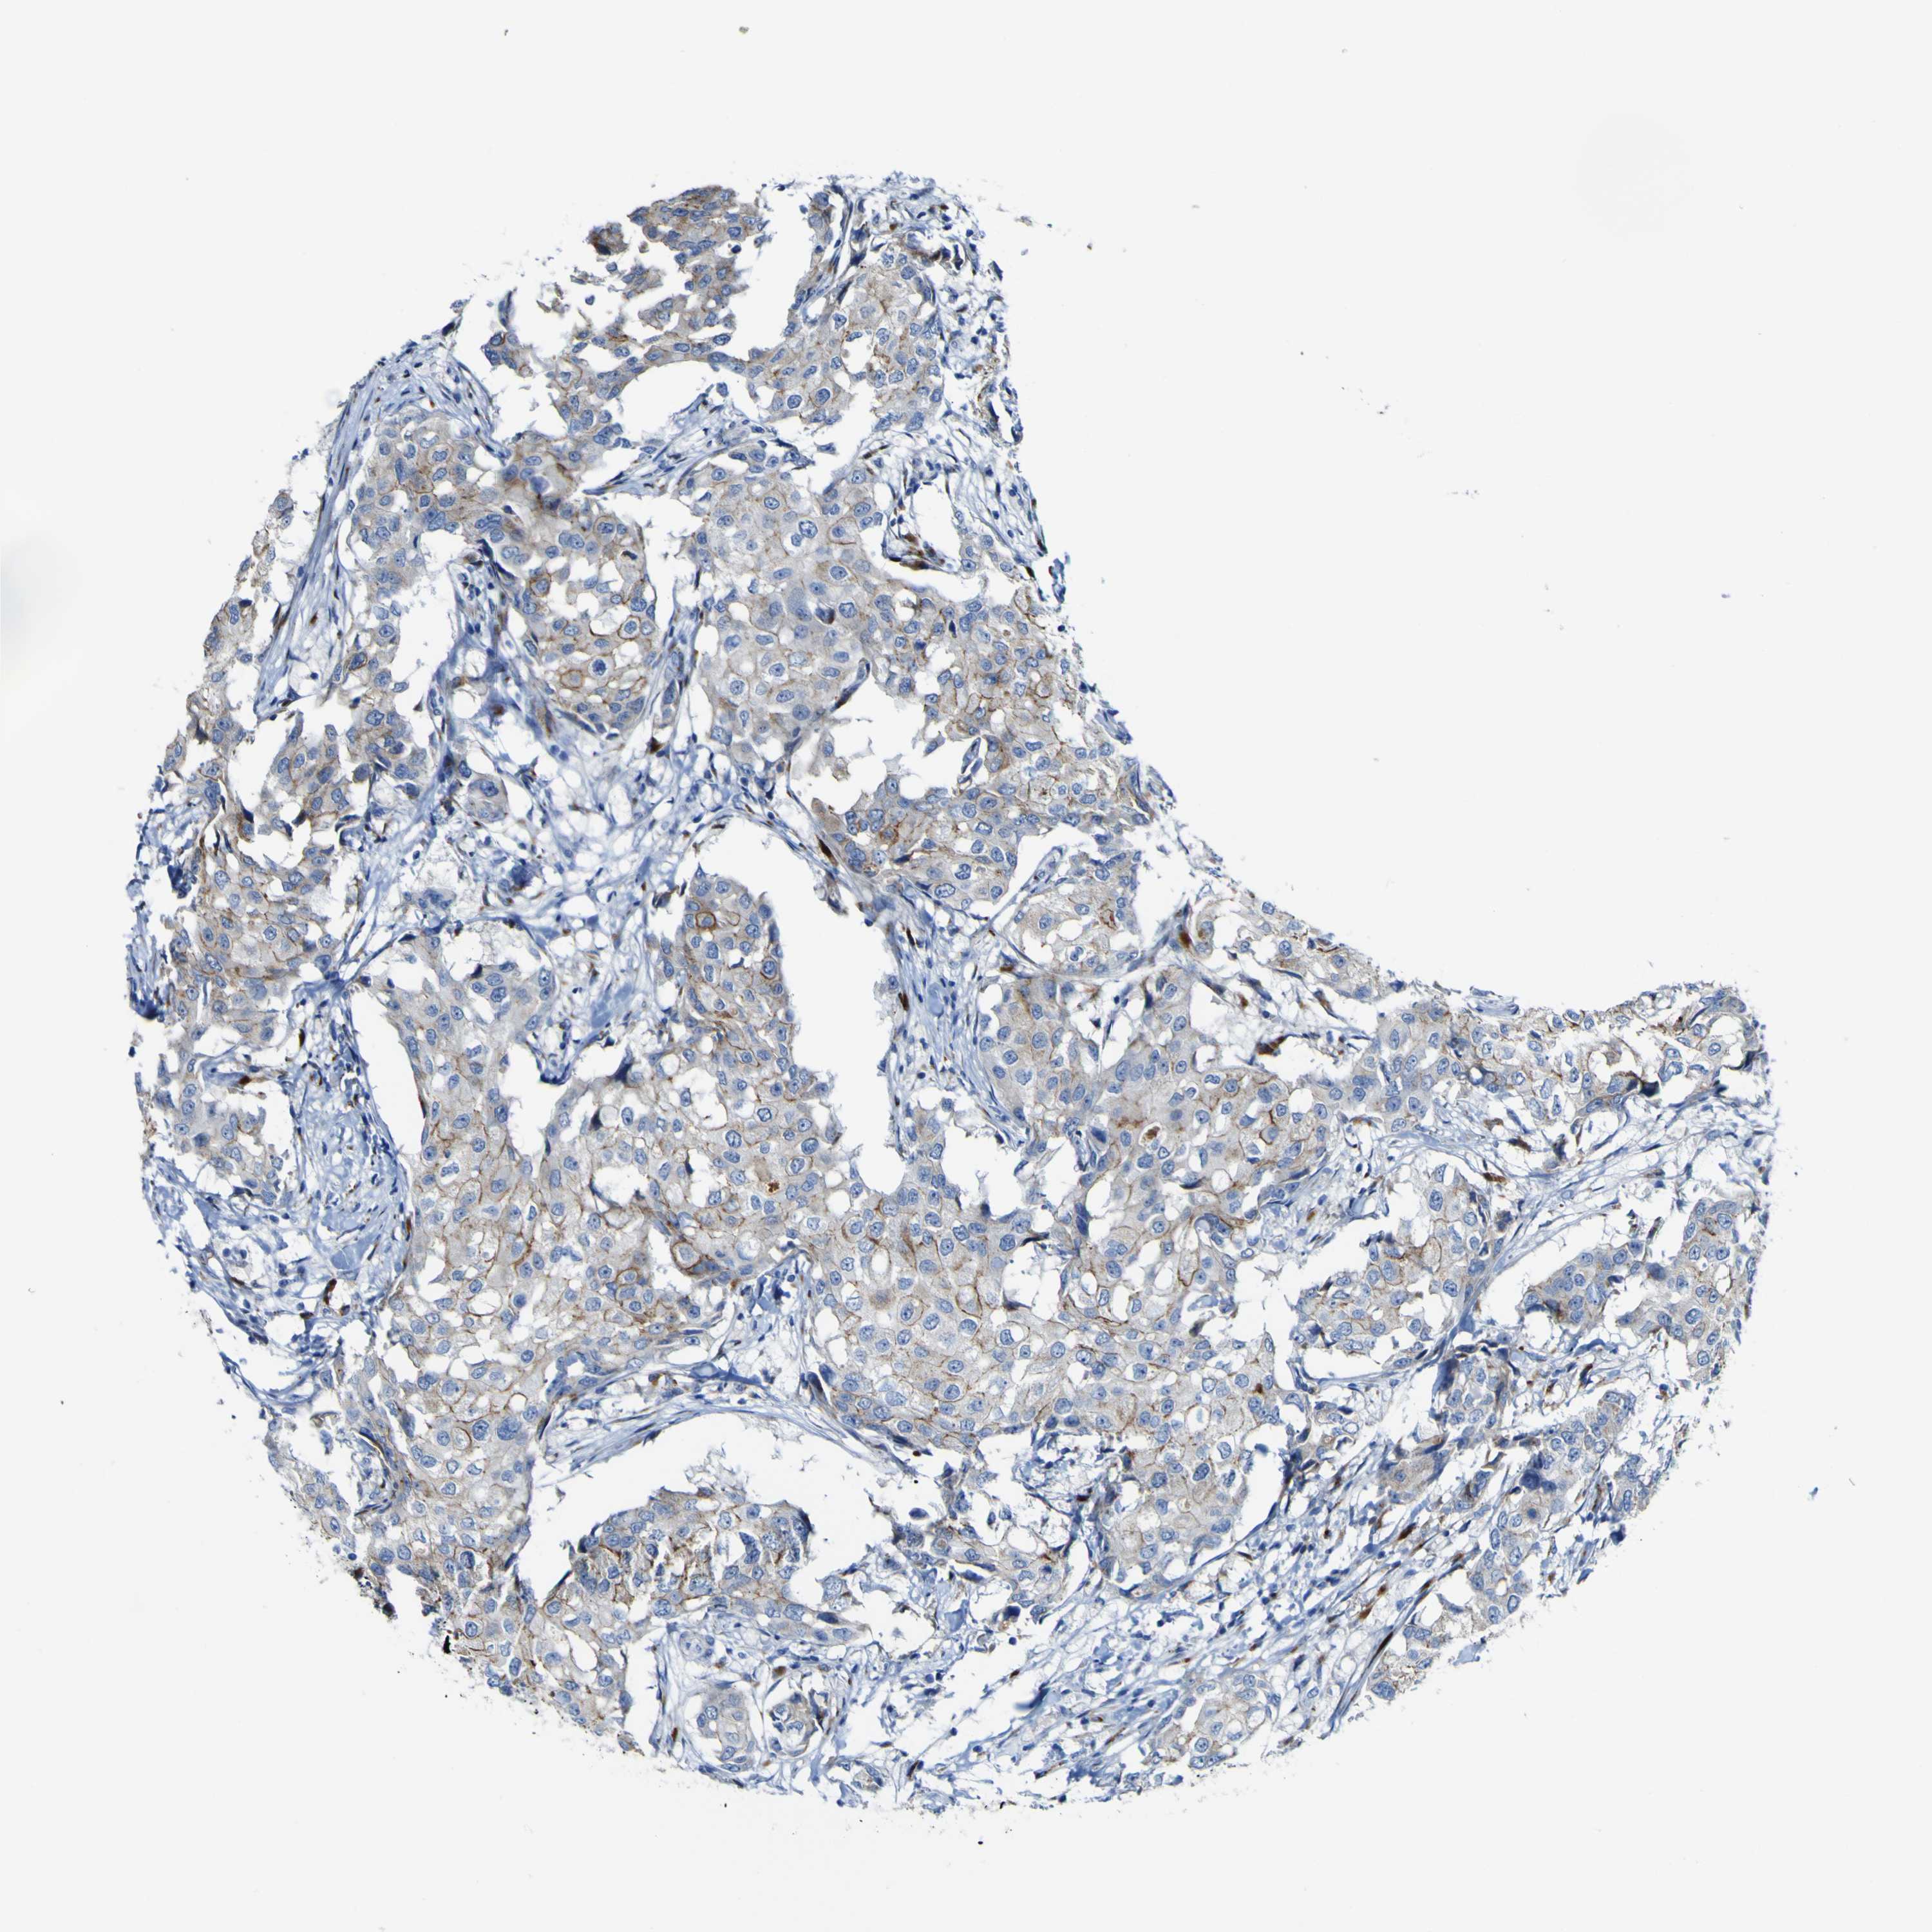

CANCER BREAST CANCER Show tissue menu

BRCA TCGA BRCA VALIDATION PROTEIN EXPRESSION